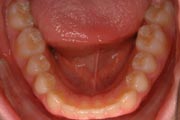

Crowding

After